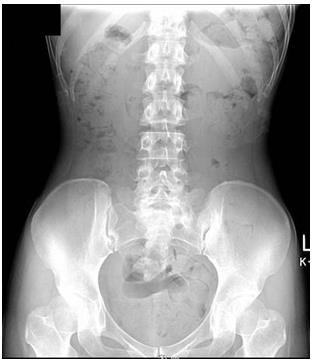

腹部X線檢查(俯臥)

體型偏瘦。大便中有空氣,可推斷糞便停滯。從盲腸到橫結(jié)腸,降結(jié)腸,乙狀結(jié)腸,直腸,以及直腸到結(jié)腸部分都有糞便停滯。診斷宿便過多。